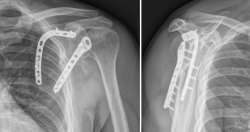

Figura 3. Radiografías anteroposterior (A) y lateral (B).

Presentamos el caso de un varón de 35 años, cerrajero de profesión y diestro. Sin antecedentes medicoquirúrgicos de interés. Sufre una caída desde un andamio de aproximadamente 2 metros de altura. Como resultado, es diagnosticado de una fractura de escápula en varios fragmentos, fractura del sexto arco costal derecho y una fractura no desplazada del ala sacra derecha. Las imágenes de la radiografía simple, de la TC y su reconstrucción 3D se muestran en las Figuras 3, 4 y 5.

Figura 11. Control radiográfico al final del seguimiento (7.º mes postoperatorio).